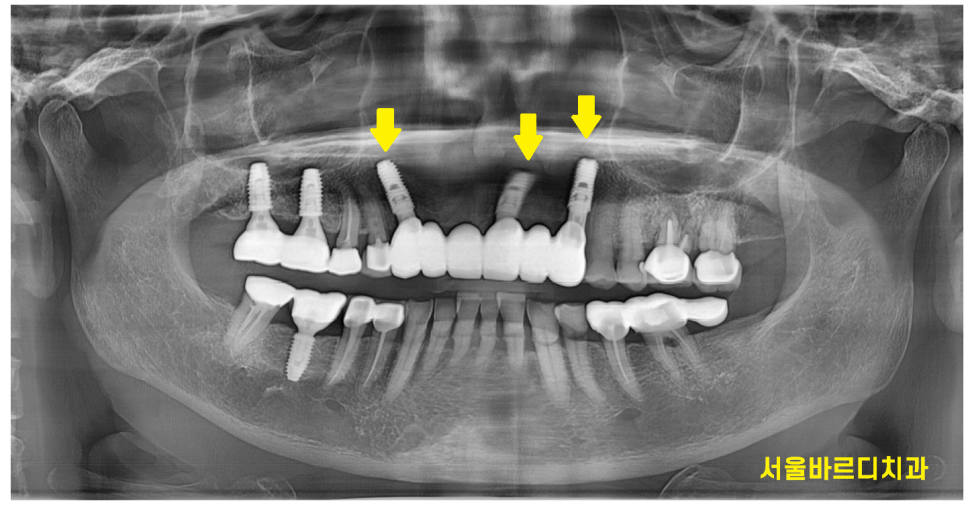

240731

4월에 수술을 하고 3개월정도 지나

머리를 만들어 드렸는데요.

똑같이 6개를 묶은 앞니 브릿지 형태인데

임플란트는 3개를 심어 6개로 만들어 드렸습니다.